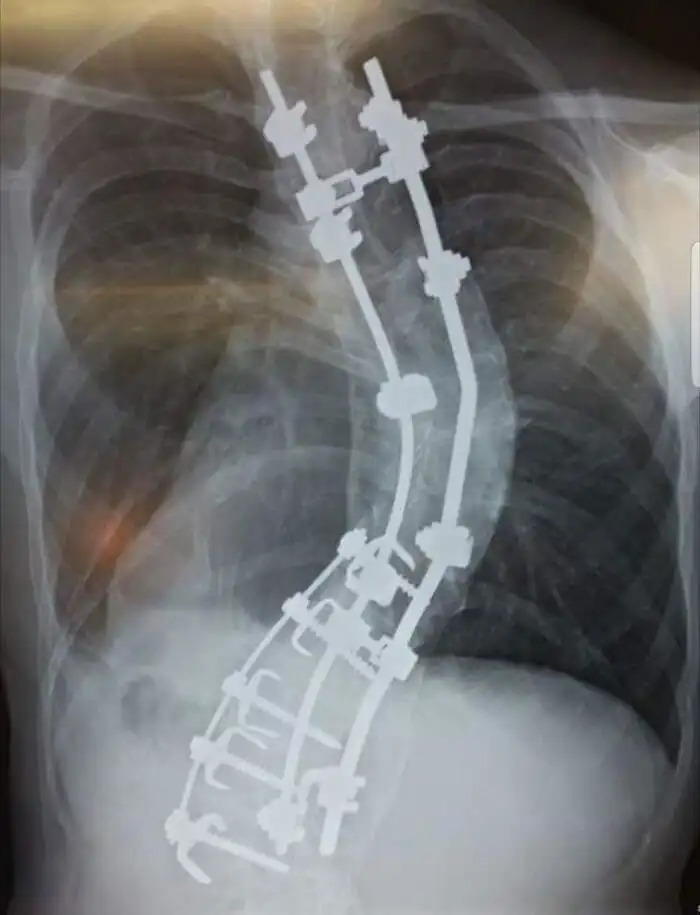

24. "Мой позвоночник. Мой рост был 178 см, когда я ложился под нож, теперь мой рост 188 см. А изначально должен был быть 2 метра"